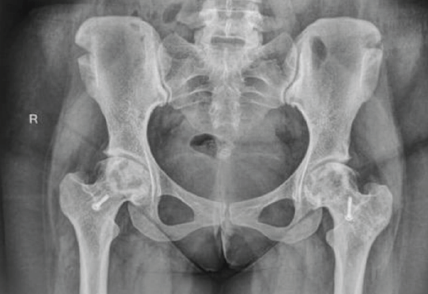

There was bilateral ON of the hips (stage 2 of Ficat-Arlet classification [8]) with greater involvement of the right femoral head than the left (Fig. 2).

Figure 2: Pre op MRI both hips. 1.5 T. Short tau inversion recovery coronal image showing ill defined geographic hyperintensities (right > left) in femoral head, femoral contour, and joint space maintained. Suggestive of avascular necrosis of both femoral heads (Ficat-Arlet II) (Right > Left).

With these findings, a diagnosis of MSON was made. Investigations were conducted to exclude underlying conditions commonly associated with MSON, which included an evaluation for connective tissue diseases: Complete blood count, erythrocyte sedimentation rate, C-reactive protein, renal function test, rheumatoid arthritis factor, anti-nuclear antibodies, anti-ds DNA, lupus anticoagulant, and anticardiolipin antibodies; an assessment of coagulation profile: Prothrombin time, activated partial thromboplastin time, international normalized ratio, fibrinogen, antithrombin, protein C, protein S, factor V Leiden, and factor VIII; and testing for viral markers (HIV, Hepatitis B virus, Hepatitis C virus), all of which returned negative results, thereby ruling out any underlying diseases. The patient’s history ruled out drug usage, alcohol usage, and exposure to hyperbaric environments (eliminating Caisson’s disease). She underwent core decompression and bone marrow aspiration concentrate (CD and BMAC) application sequentially in all affected joints in 3 sessions with a 2-month gap. Shoulders were first addressed, and knees and ankles were addressed last, and advised Alendronate 70 mg once a week after shoulder surgery for 3 years. When evaluated after 18 months of surgery, the pain Visual Analog Scale (VAS) in the shoulder decreased from 9/10 to 0/10 (Fig. 1c). In the hips, VAS of 6/10 decreased to 0/10 after 1 month of surgery. But after 9 months, it gradually increased to 9/10. Radiological assessments indicated that both hips advanced to Stage III, with the right hip showing a greater deterioration than the left (Fig. 5). Thus, she underwent TFL muscle pedicle bone grafting to both hips after 2 years of primary surgery, following which VAS scores gradually decreased to 2/10 on the right side and 0/10 on the left side (Fig. 6). VAS decreased from 9/10 to 4/10 in the right ankle and from 9/10 to 4/10 in the right knee. The left ankle and knee remained pain-free in both pre-operative and post-operative periods. The patient is walking independently now.

Figure 5: Magnetic resonance imaging of both hips post-core decompression. 1.5 T. Short tau inversion recovery, coronal, showing heterogeneous hyperintense signals in both femoral heads with loss of contour of femoral heads (right > left) and joint space maintained, suggestive of Ficat-Arlet III stage of avascular necrosis. Stigmata of core decompression were seen at both femoral heads.

Figure 6: Digital X-ray of pelvis with both hips showing avascular necrosis of both femoral heads operated with tensor fascia lata muscle pedicle graft.

ON is believed to result from ischemia of the juxta-articular bone, usually occurring in the second through fifth decades [9]. According to the Collaborative ON Group Study, 91% of cases of MSON are caused by steroids [10]. Steroid dosage and route of administration appear to be closely related to the development of MSON. In our case, the major factor contributing to the MSON was prolonged corticosteroid use. In terms of anatomic distribution, MSON most commonly affects the femoral head, followed by the knee, shoulder, and ankle. In our case, the ankle and shoulder were affected first, followed by the remaining joints. Most patients have pain on the affected site, but up to 33% have asymptomatic ON. Magnetic resonance imaging is the gold standard diagnostic method to detect both symptomatic and silent ON [11] and is essential for assessing the severity of the disease and informing treatment strategies. The degree of epiphyseal involvement, categorized by various classifications as <15%, between 15% and 30%, or exceeding 30% of the epiphyseal volume, serves as the most reliable indicator of potential bone collapse [12]. The advancement of ON can vary significantly among different joints. Notably, the femoral head tends to progress at a rapid pace, necessitating careful monitoring for the early onset of symptoms. In contrast, the progression in the elbow and wrist occurs at a comparatively slower rate [4]. The ideal management of ON in a young individual remains a subject of debate. Typically, conservative approaches are employed when there is no indication of joint collapse, such as the use of non-steroidal anti-inflammatory drugs (NSAIDs) and limiting weight-bearing activities. In addition, various surgical interventions have been suggested based on the disease’s progression. These interventions encompass CD, both vascularized and non-vascularized grafting, osteotomy, and ultimately, arthroplasty as a last resort [13]. It is essential for patients to undergo follow-up assessments for 2 years to evaluate the condition of the adjacent joint and to consider total joint replacement if necessary. Review of literature supports CD as an effective treatment option in the pre-collapse stage of ON in small to medium-sized lesions according to Ficat and Arlet Stage-I and II [14]. In the advanced stages of the disease (i.e., Stages III and IV), arthroplasty is required when joint preservation is not possible [4]. A recent systematic review on CD showed 78%, 59%, and 27% success rates in Stages I, II, and III, respectively [15]. Alendronate is the preferred medication for this relentlessly progressive condition, irrespective of the stage at which patients are diagnosed, as it alters the natural progression of AVN of the hips and delays the necessity for arthroplasty [16]. Hence, we advised taking sodium Alendronate 70 mg once a week. In this case, CD and BMAC were done as all the joints were in Stage II. Post-surgery, the shoulder joints are pain-free. She is experiencing intermittent pain in her hip joints twice or thrice a month, which can be managed with NSAIDs. VAS scores for both hips improved within a month of surgery, yet after 9 months, the score increased as both hips progressed to stage III. This suggests CD and BMAC was unsuccessful. We can infer that, as her condition improved drastically after the second surgery, TFLMPG, it would have been better to perform it instead of CD and BMAC. This would have avoided the need to perform a second surgery. Her right knee and ankle pains only on walking for prolonged periods of time, which can be controlled by NSAIDs. Now she is able to walk independently, do her daily activities, and her overall quality of life has improved significantly.